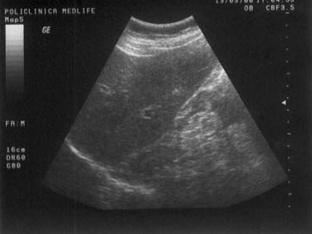

Ecostructura neomogena

Este rezultatul modificarii arhitecturii tisulare a unui parenchim. De exemplu, nodulii regenerativi au, frecvent, o densitate diferita de cea a parenchimului normal si returnarea ecourilor de la acest nivel este crescuta. Imaginea de ansamblu a planurilor de sectiune se caracterizeaza prin neomogenitate.